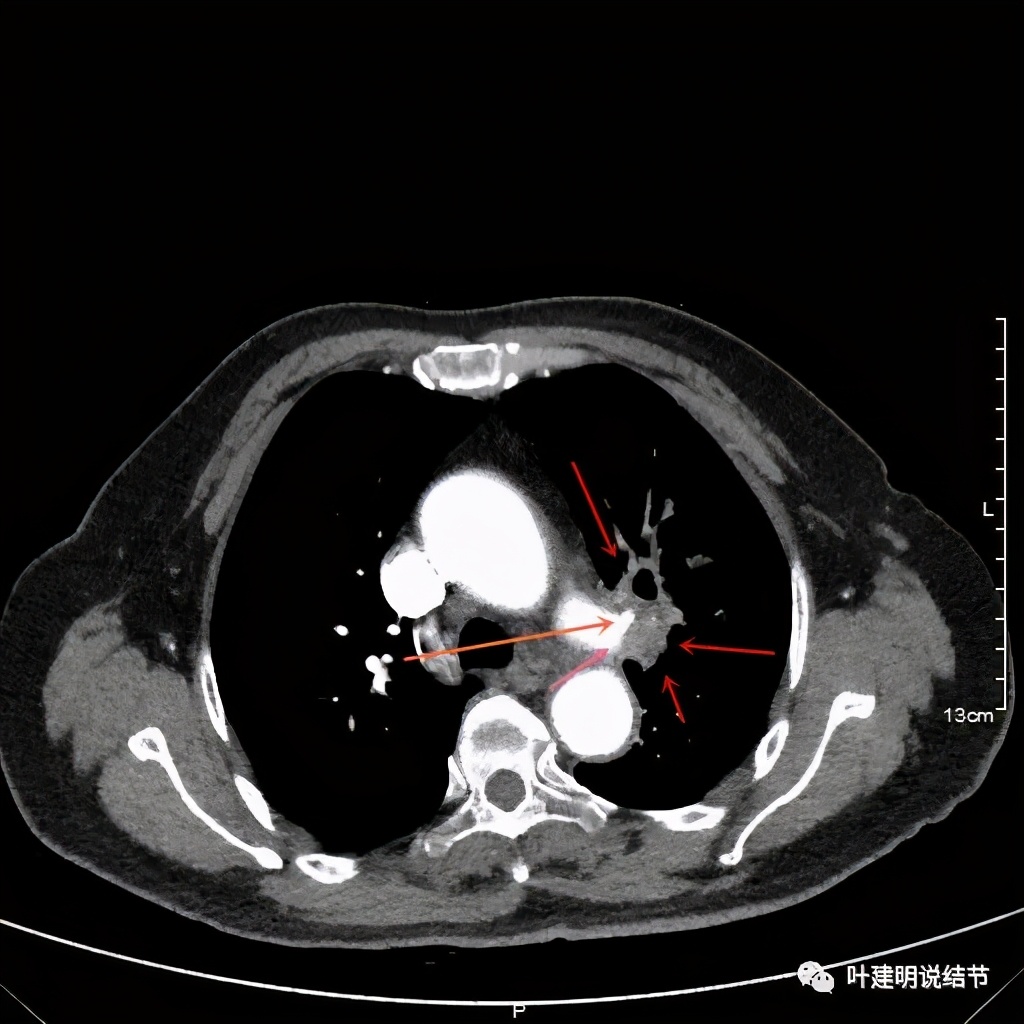

上图桔色箭头示左肺动脉分支处仍被软组织(原肿瘤所在)包绕,粉色箭头示肺动脉仍与肿瘤处关系密切

上图也示桔色箭头示左肺动脉分支处仍被软组织(原肿瘤所在)包绕,粉色箭头示肺动脉仍与肿瘤处关系密切

上图示肿瘤部位仍与肺动脉关系密切,似乎未能脱开,红色示肿瘤处